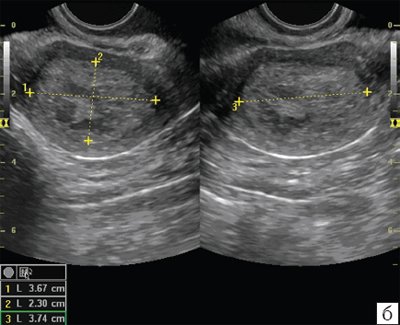

Медицинская диагностика: Гиперплазия эндометрия на УЗИ